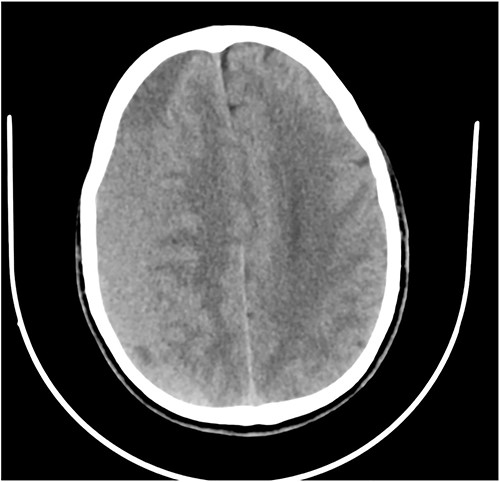

Prior to this, he had been managed for low back pain and lumbar spondylosis. Spine MRI done prior to neurosurgery consultation did not explain the lower extremity motor weakness. Brain CT done revealed bilateral fronto-parietal CSDH (Fig. 2A). He was worked up for urgent surgical evacuation through a bilateral frontal and parietal burr hole drainage. He made good neurologic improvement and his lower extremity power returned to normal on the 8th day post op. Post-operative CT scan done at 4 weeks follow-up showed satisfactory resolution of the haematoma (Fig. 2B).

(A) Pre-op showing bilateral CSDH. (B) Post op complete resolution of CSDH.